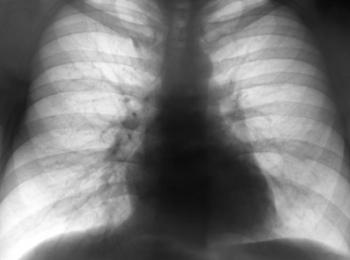

It’s believed that AATD affects an estimated 120,000 Americans. Unfortunately, only about six percent of those with AATD are correctly diagnosed because the symptoms resemble chronic obstructive pulmonary disease (COPD), or emphysema, and it often takes years.

Two genetic variants in the SERPINA1 gene — called PI*Z and PI*S — lead to more than 95 percent of all cases of AATD. Those variants can decrease the transport of protein alpha-1 antitrypsin enzyme from the liver to the lungs. The protein is sent through the blood to the lungs to help protect lung tissue. Low levels in the lungs can lead to damage. In contrast, abnormal levels of alpha-1 antitrypsin in the liver can cause damage to the liver. Symptoms may include shortness of breath, wheezing, or infections in the lungs or liver. Other symptoms might include yellow skin, fatigue, rapid heartbeat, vision problems, or weight loss.